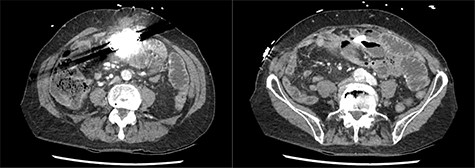

A presentation 6 weeks later was once again diagnosed as ASBO, with multiple segments of dilated small bowel with a transition point identified in the right iliac fossa on CT scan (Figs 1 and 2). On this occasion, operative management was required, with the AICD identified to the left of the umbilicis with extensive matted adhesions to small bowel encountered. Extensive adhesiolysis was undertaken at this area, with the defibrillator removed from the intra-abdominal cavity and repositioned in a subrectus pocket. Following the procedure, the AICD was reactivated and confirmed to be operating as expected. The patient responded well to operative management and began opening his bowels on the third day postoperatively. The patient tolerated a diet and was able to be discharged home. He was reviewed in the clinic 6 weeks after the laparotomy, and at this time it was found he had continued to open his bowels regularly and was undertaking his usual activities with nil issues. The patient had not had any further episodes or symptoms concerning for obstruction.

Axial slices of computed tomography scan showing beam hardening artefact from intra-abdominal AICD, adjacent to distended loops of small bowel.